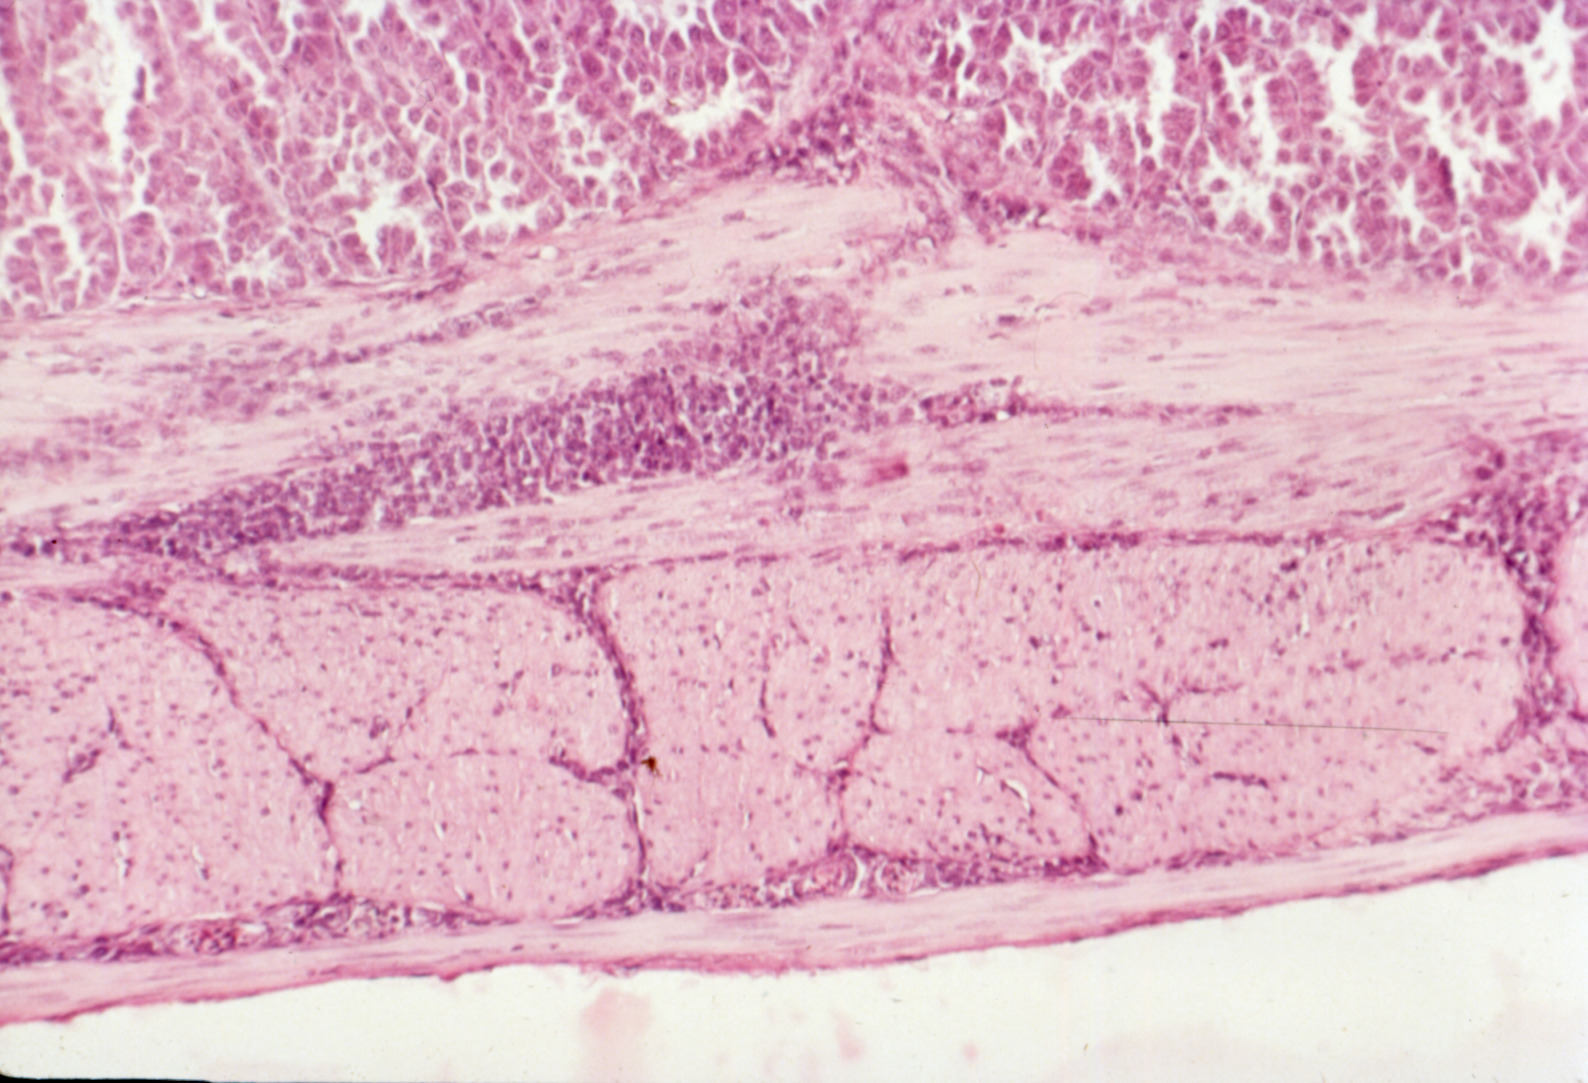

Avian encephalomyelitis (slide study set no. 5)

Avian encephalomyelitis Avian medicine Chickens--Diseases Turkeys--Diseases Pheasants--Diseases

Slide Study Set #5, Avian Encephalomyelitis, 2 sets (includes 32 color slides), 1974